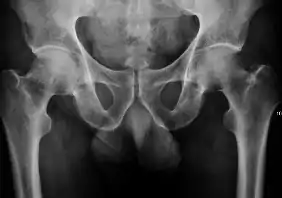

Projectional radiography ("X-ray") is the first imaging technique of choice in hip pain, not only in older people with suspected osteoarthritis but also in young people without any such suspicion. In this case plain radiography allows categorization as normal hip or dysplastic hip, or with impingement signs, pincer, cam, or a combination of both.[1]

Projectional radiography ("X-ray") is currently useful not only in older people in whom osteoarthritis of the hip is suspected but also in younger people without osteoarthritis, who are being evaluated for femoroacetabular impingement (FAI) or hip dysplasia.[1]

Plain radiography allows us to categorize the hip as normal or dysplastic or with impingement signs (pincer, cam, or a combination of both). Besides these, pathologic processes like osteoarthritis, inflammatory diseases, infection, or tumors can also be identified (Figure 1).[1]

X-ray in adults

- Hip dysplasia

Measurements of hip dysplasia in adults are quite different from those in children.[1]